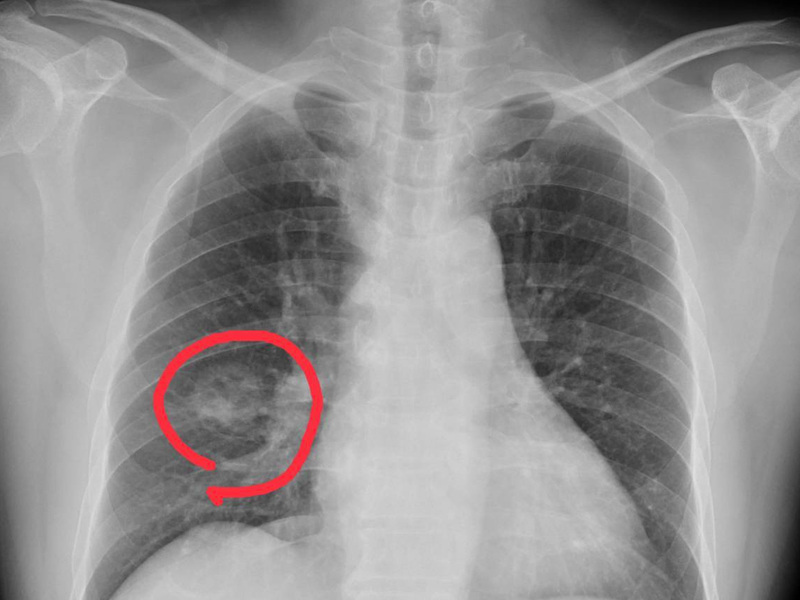

4. 關節疼痛

在肺癌晚期,腫瘤細胞可通過血液循環等途徑轉移到骨中,引起骨損傷和骨膜神經損傷,可引起局部劇烈疼痛症狀,如手足關節疼痛,也可導致病理性骨折,加重疼痛症狀。